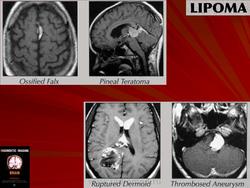

Липома

Это редкие и доброкачественные опухоли, состоящие из жировой ткани. Они происходят из несформированной жировой ткани во время формирования нервной трубки у плода. На уровне головного мозга, типичны в области мозолистого тела. Обычно обнаруживаются в ходе случайных исследований КТ или МРТ, произведенных по другим причинам. Могут быть ассоциированы с другими пороками развития ЦНС. Они не требуют никакого лечения.

Существуют также спинальные липомы, особенно спинномозгового конуса и конского хвоста. Они могут давать симптоматические проявления в детском и подростковом возрасте, так как блокируют спонтанное продвижение спинного мозга внутри позвоночного столба, второстепенное росту. В этих случаях наблюдаются признаки и симптомы такие, как паралич нижних конечностей и сфинктерные расстройства.

Лечение хирургическое и состоит в предоставлении возможности продвижения спинному мозгу, без попыток удаления липомы, внутри которой присутствуют нервные корешки.

Перикаллозальная липома